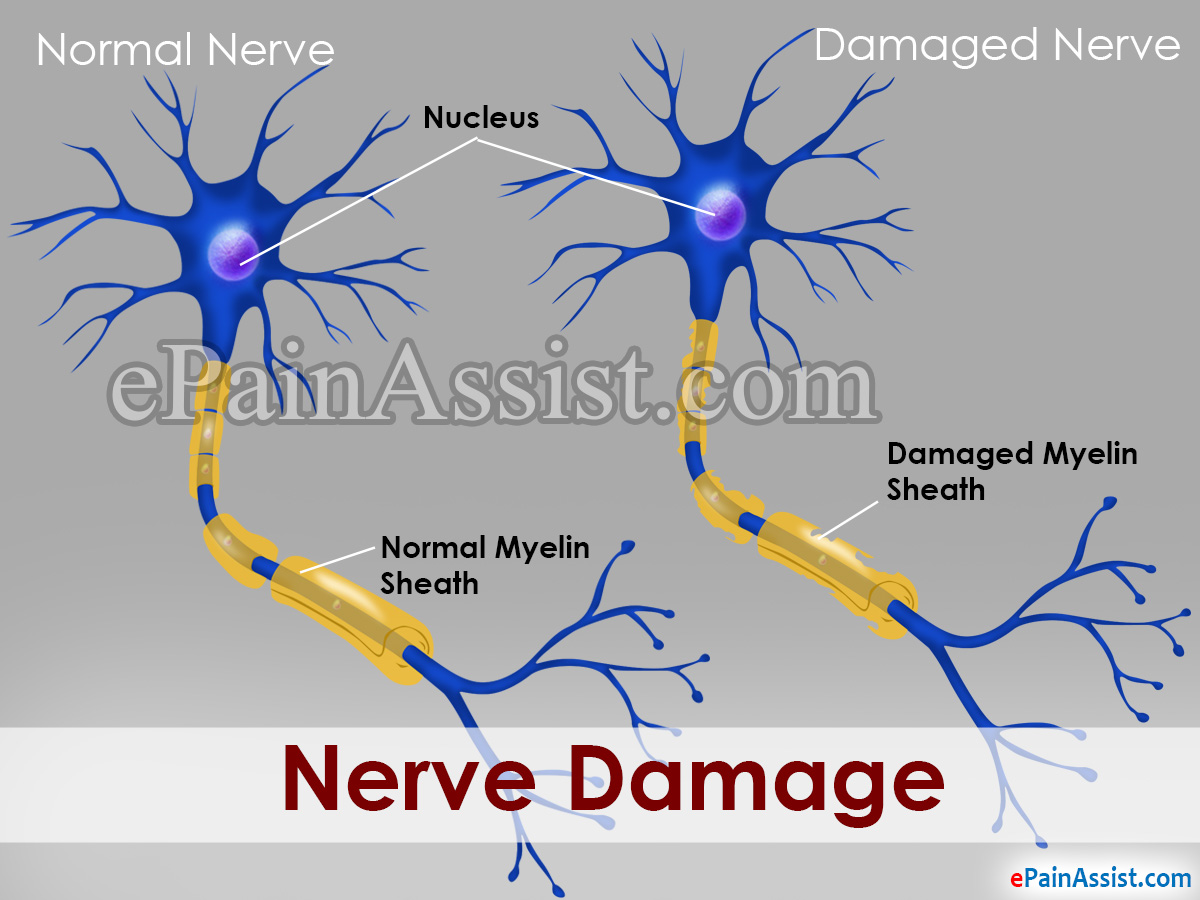

The outer epineurium is stronger than the other layers and often remains intact (unbroken). A nerve injury can affect the brain's ability to communicate with muscles and organs. However, the complex inner layers of the nerve are disrupted.

These injuries are usually found in laceration or severe stretch injuries. By amino science posted on: Peripheral nerves are fragile and easily damaged.

After that, a nerve can be. Broken nerve fibers or more severe injuries: This can benefit nerve function.